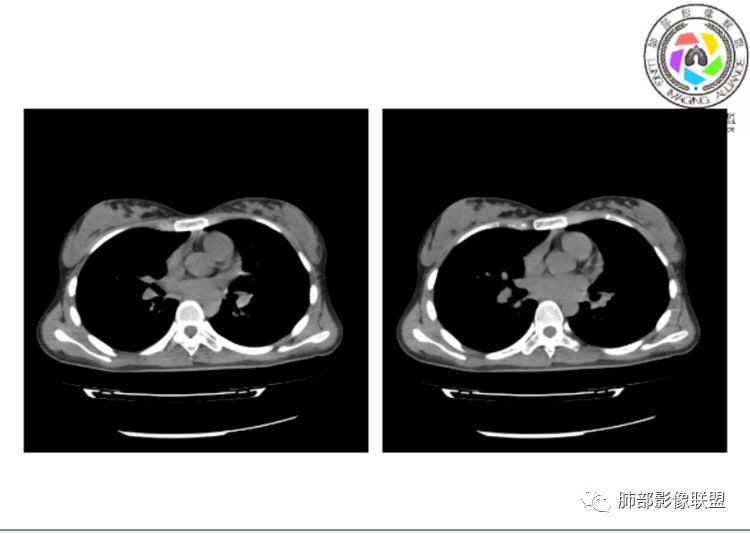

小微:右肺下叶斑片状密度增高影,抗炎治疗6天后复查,双肺下叶出现斑片状密度增高影,排除炎性病变,D2聚体特别高,考虑肺栓塞,肺梗死,建议增强扫描。王开金江津中心医院呼吸科:@岳微-辽宁PLA234医院放射科?支持,患者年轻女性,胸痛主诉,使用雌激素,高危人群,心率快,d二聚体升高,右下叶斑片加肺动脉明显增宽,抗感染无效,要考虑PTE,建议肺动脉ctpa。傅昌瑜:19岁,女性,右侧胸痛2天,发热以中度热为主,D—二聚体升高,肺动脉主干增宽,病灶位于胸膜下,抗感染后增多,近来有服用炔雌醇环丙孕酮片2周期史,诊断:肺栓塞,下一步完善肺CTPA检查。阿仙奴:青年女性,急性起病,胸痛入院,月经不调史,目前服用孕酮片。流感抗体阳性,d二聚体升高,无低氧血症。右肺下叶基底段胸膜下磨玻璃样改变,肺动脉增宽,治疗过程出现发热,复查左下叶胸膜下新发病灶。考虑:肺栓塞(服用孕酮相关)?奔跑的37°Doctor(陆喜红 ) :年轻女性,胸痛 急性病程,有服用雌激素避孕药史(是否有血液循环的改变,高凝状态),实验室D二聚体很高(也是提示血液高凝状态) ,第一次CT,右下肺胸膜下斑片状密度增高模糊影,肺动脉形态密度未见明显异常,抗炎后复查,肺动脉干及其分支,感觉增粗了一点,局部形态有点饱满,双下肺胸膜下片状影增多,锁定肺动脉栓塞应该不会错,建议CTA检查飞鹰行动:青年人,女性,右肺下叶斑片状密度增高影,抗炎治疗6天后复查无好转,,双肺下叶出现斑片磨玻璃影,主肺动脉增粗,结合患者服用的药物和D2聚体特别高,考虑肺栓塞,建议CTA。李:口服避孕药,有危险因素,肺动脉较主动脉增宽,D二聚体增高,胸膜下片状影,考虑肺栓塞;@晨义工张帅,医附属潞河医院呼吸?是否痰中带血很关键,不知有没有张帅:患者入院后第七天出现痰中带血风之子:病程中有发热,D—二聚体升高,肺动脉主干增宽,病灶分布于胸膜下,抗感染后增多,结合服药史诊断:肺栓塞,建议CTPA检查。不支持的地方是没有低氧血症,不明白为什么第二次复查ct双侧乳腺不对称,按理乳腺炎多见于哺乳期张帅:大家方向都在考虑肺栓塞:我提问两个问题:1 周围毛玻璃怎么回事?2左下肺小叶间隔增宽怎么回事?笨丫头:周围的磨玻璃应该考虑是肺梗死后出血渗出,同时合并机化性炎症小叶间隔增宽,我考虑应该是梗死后炎性渗出wonderful:我不支持肺栓塞 不能解释发热原因

笨丫头:肺栓塞也会发热呀王江涛:肺内子宫内膜异位症,合并梗死出血Lenle董:外围渗出性改变,出血?左下肺的支气管镜不会看张帅:呼吸困难比较难判断,尤其对于一个有胸痛的患者来说@唐大川新沂市人民医院呼吸科风之子:对,要警惕子宫内膜异位症岁月:病史:女,19岁;右侧胸痛2天;血常规17.4,中性粒75.7%,右下肺斑片影;月经不调,雌激素?治疗;D2高,3974.78,支气管镜阴性。治疗方式,抗炎。病史诊断方向:肺栓塞?影像:首先找肺栓塞影像。6天后CT可疑肺栓塞;作者量肺动脉23.7mm,提示什么?好像和同层面主动脉宽度相当,先心病?肺血无明显改变?双肺斑片影,左侧磨玻璃,边界清楚,还有些散在不清楚,左侧为甚,胸膜下贴,三角形?左侧少了胸水;诊断:肺栓塞;鉴别:先心合并肺栓塞?肺炎。

张帅:好多老师都在说肺动脉增宽。肺动脉增宽标准是多少?程磊:29。或者比同层主动脉比值大于等于1

张帅:我量的虽然不标准,但不到24

CT平扫及间接征象:

1、一个或多个胸膜下斑片高密度影(梗死、出血、肺不张、肺水肿、炎性渗出),典型为胸膜下楔形影 ,尖端指向肺门

2、肺动脉高压(中心肺动脉扩张),有时可见肺动脉区高密度影。

3.影像:病变胸膜下多发斑片影,提示与血管有关,早期病变为渗出,应该是早期的炎性渗出,病灶抗感染治疗后实变区增多、变大,临床症状又出现咯血,CT上应该合并了肺泡出血、梗死、肺不张及肺水肿;